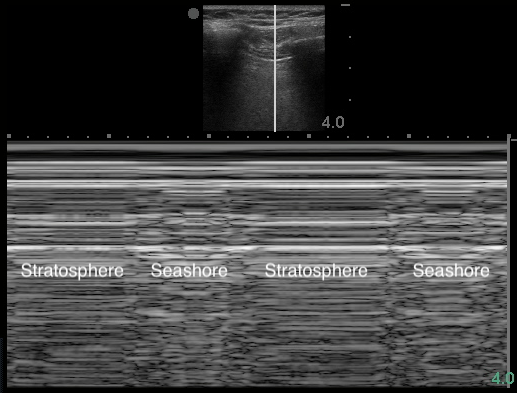

Lung Sliding

- Horizontal to-and-fro sliding movements of the visceral pleura in synchrony with respiration along the directly apposed parietal pleura, as seen in B-mode

- Can also be visualized in M-mode (Image 8) and using power Doppler61 (Video 4)

- Figure 8. Seashore sign

- Lung sliding rules out PTX16

Pneumothorax

- Sonographic signs include:10,11

- Absence of lung sliding

- Figure 16. Stratosphere sign in M-mode

- Air within pleural space scatters the sound waves. The stationary parietal pleura attached to the chest wall is still visualized, but the visceral pleura is not.

- Highly sensitive but not specific for PTX11,58